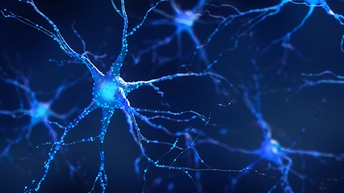

Think neuroscience

Scientists, philosophers, and artists alike are mesmerized by the brain, likening this 3 lbs of matter to a computer, a great factory, a beautiful mess, a world of unknown territory —or the most complicated object in the known universe. To even begin to understand the complex structure and function of the nervous system, including the brain, neuroscience researchers need to rely on innovative technologies, including analytical, cellular, and molecular biology, and imaging technologies.